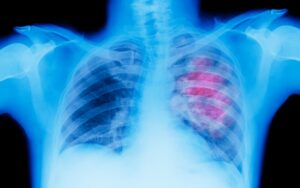

La detección temprana juega un papel fundamental en el tratamiento exitoso del cáncer de pulmón. Aunque en etapas tempranas la enfermedad puede no presentar síntomas evidentes, los estudios de imagen como la tomografía computarizada (TC de baja dosis) pueden ayudar a identificar posibles anomalías en personas con alto riesgo, como los fumadores actuales o quienes han fumado durante muchos años.